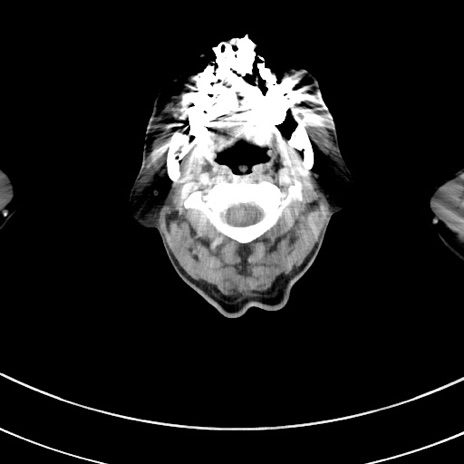

症例8(横断像)

【症例】 60歳代男性

【主訴】 黒色吐物

【現病歴】 4日前から嘔気自覚、2日前の朝食後にも嘔気あり、自分で手で嘔吐反射起こし嘔吐したところ血が混ざっていたため受診。

【既往歴】 5年前汎発性腹膜炎を伴う急性虫垂炎で手術、高血圧、前立腺肥大症、高脂血症

【身体所見】 腹部正中に手術癩痕あり 腹部平坦・軟圧痛なし膨満感あり

【データ】WBC 8400、CRP 4.54